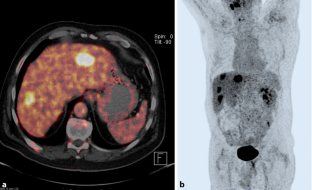

Abb. 1

Abb. 2

Abb. 3

Abb. 4